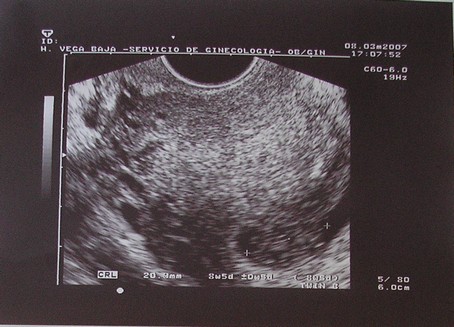

Nagyon jó az UH!!!!!

.... Egyébként B babát én nem igazán látom jól...